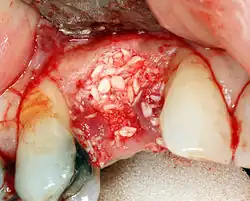

Реконструкция твёрдых тканей

Если ширина кости недостаточна, она может быть выращена с использованием искусственных или кадеварных кусочков кости, чтобы выступать в качестве основы для роста естественной кости.

Когда требуется большее количество кости, её можно взять из другого места (обычно задней части нижней челюсти) и пересадить на участок имплантата.

Верхнечелюстная пазуха может ограничивать высоту кости в задней части верхней челюсти. С помощью «синус-лифтинга» костная ткань может быть привита под синусную мембрану, увеличивая высоту кости.